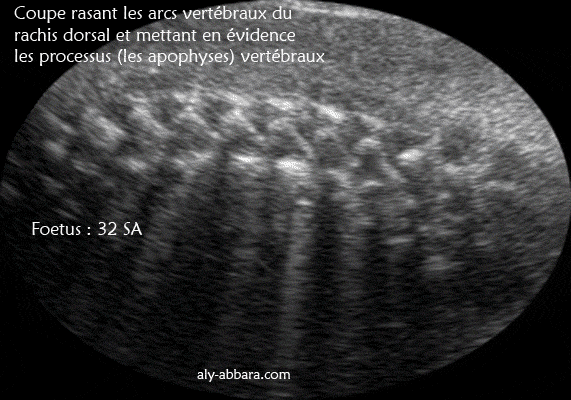

Rachis dorsal : coupe rasant les arcs vertébraux et montrant les processus (ou les apophyses épineux et les processus transverses

Image échographique montrant les processus (les apophyses) des arcs vertébraux du rachis dorsal, il s'agit des processus épineux et des processus transverses.

Foetus de 32 SA d'âge.